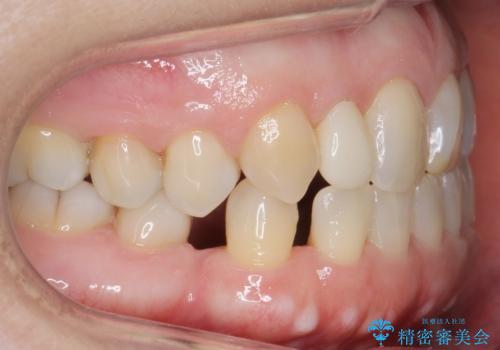

矮小(わいしょう)歯の形をセラミックで自然に 50代女性

- 右上の2番目の前歯がとがった形をしていたため、セラミックで形を整えています。

短くてとがった歯の形が反対側と同じ形となり、左右対称となり、ずいぶん自然な印象になりました。

下の前歯とのかみ合わせが切端咬合だったため、前歯の部分矯正も併せて行っています。(費用別途)